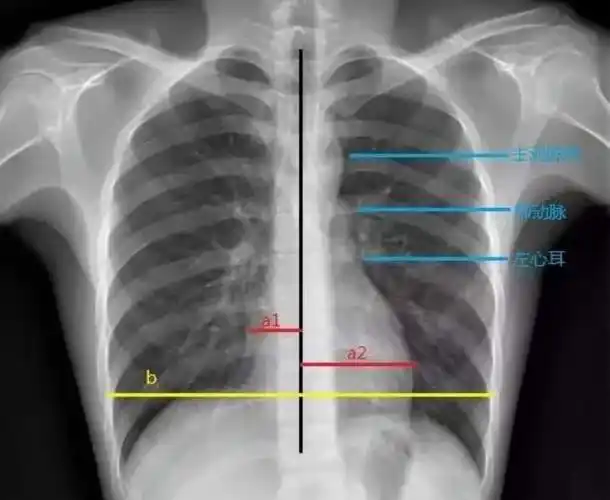

临床执业医师实践技能考试心脏增大诊断公式

【求助】普大型心,梨形心,靴形心的片子究竟怎么看啊